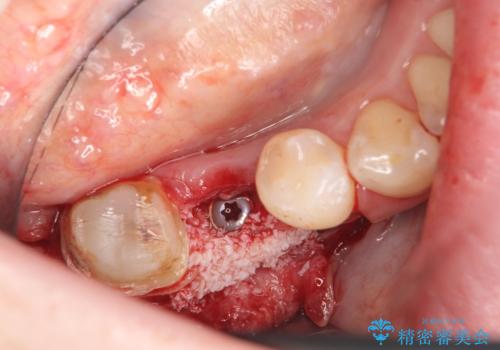

右下7は欠損しており、右下5は保存不可能だったため、インプラントによる欠損補綴を行いました。

インプラント埋入時には骨が不十分な部位に骨増生を行っております。

当院では主にストローマンという種類のインプラントを治療に用いています。

ストローマンは世界的にもNo1のシェアを誇り、骨との適合にも優れたインプラントです。

カスタムアバットメントは患者様それぞれの歯茎に合わせて製作されたオーダーメイドのアバットメントです。

既製のアバットメントに比べ適合がよく、高い清掃性を誇ります。